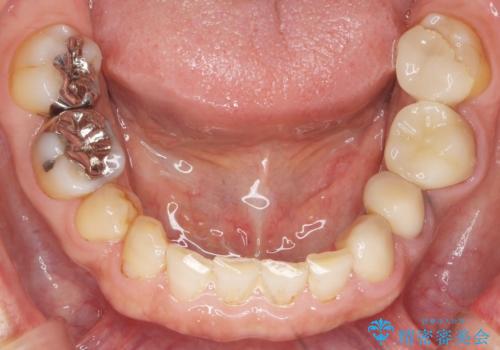

- 奥歯の被せ物をセラミックにしたいとご希望され、来院された患者様です。

左下の奥歯(左下6)の劣化した白い被せ物と金属の土台を除去し、セラミッククラウンによる補綴治療を行いました。

セラミッククラウンの天然歯のような自然な仕上がりと咬み心地に喜んで頂けました。

クラウンの種類:オールセラミッククラウン スタンダード